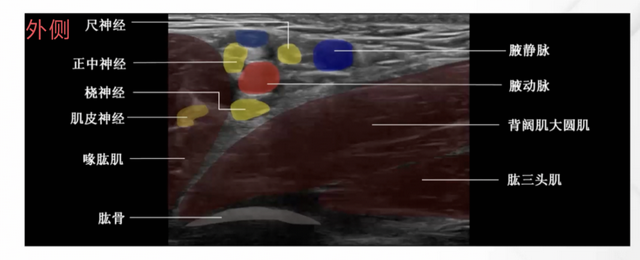

臂丛神经由C5 - C8颈神经前支和T1神经前支大部分构成,经前、中斜角肌间隙,走行于锁骨下动脉后上方,经锁骨后方进入腋窝,在此分成三个主要神经干。三干在锁骨后第一肋骨中外缘处各分成前后两股,六股神经在腋窝处组成三束(上干、中干的前股合成外侧束,下干的前股成为内侧束,三干的后股组成后束) ,各束在喙突平面分出神经支,外侧束分出肌皮神经,后束分出腋神经和桡神经,内侧束分出尺神经和正中神经内侧头。在腋窝区,臂丛神经的终支桡神经、尺神经和正中神经与腋动脉关系密切,桡神经多位于动脉的深部,尺神经位于腋动脉的内侧,正中神经位于腋动脉的外侧 ,这是腋路臂丛阻滞的关键解剖基础。

肌皮神经来自外侧束,通常在腋鞘之外,穿过喙肱肌,在肱二头肌和肱肌之间下行,支配肱二头肌和肱肌,继续前行,发出前臂外侧皮神经。

桡神经是后侧束的终末支,经大圆肌下方,肱骨和肱三头肌长头之间离开腋窝,桡神经发出分支支配肱三头肌、肱桡肌和桡侧伸肌群,发出皮支支配手臂的外侧面、前臂与手部背面。

正中神经来自外侧束和内侧束,发出支配手和腕部屈肌的运动支,发出感觉支支配大拇指、示指、中指、无名指外侧半的掌侧。

尺神经是内侧束的终末支,与前臂内侧皮神经一同走行,开始沿肱动脉内侧下行,在中臂处与动脉分离,经肱骨内上髁后面降至前臂,尺神经发出支配肘关节的关节支和支配手部、前臂的肌支,发出支配无名指和小指的感觉支。